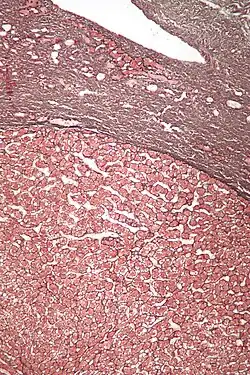

| Micrograph of a hepatic adenoma (bottom of image). H&E stain | |

Pathologic diagnosis

Hepatic adenomas are, typically, well-circumscribed nodules that consist of sheets of hepatocytes with a bubbly vacuolated cytoplasm. The hepatocytes are on a regular reticulin scaffold and less or equal to three cell thick.

The histologic diagnosis of hepatic adenomas can be aided by reticulin staining. In hepatic adenomas, the reticulin scaffold is preserved and hepatocytes do not form layers of four or more hepatocytes, as is seen in hepatocellular carcinoma.

Cells resemble normal hepatocytes and are traversed by blood vessels but lack portal tracts or central veins.

Micrograph of hepatic adenoma. H&E stain -